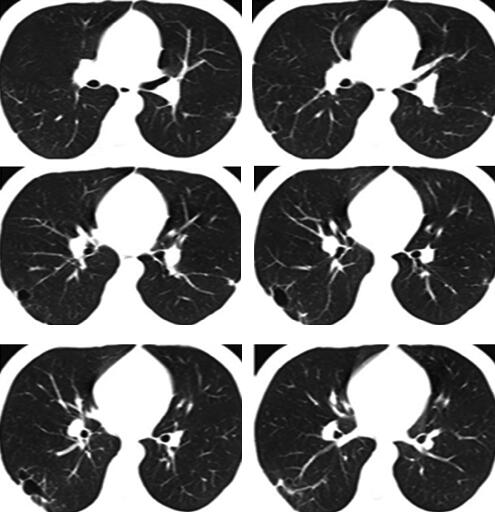

3.胸部CT:

右肺下叶外后基底段散在斑片及片状渗出影,部分病灶呈楔形,尖端指向肺门,右下叶后基底段近脊柱旁片状阴影内见密度减低区,病灶与胸膜粘连(图1)。

图1